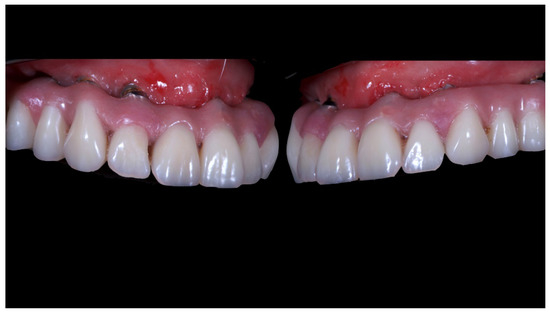

A partially edentulous 78-year-old woman with a complete screw-retained implant-support hybrid prosthesis (Figure 1) in the upper jaw and natural dentition in the lower jaw was referred to a private center in Rome, Italy, due to several continuous breakages of the prosthetic part of the implant-supported rehabilitation. After a preliminary interview, the patient stated that the implant treatment was finished two years before, but she had never been comfortable with this prosthesis (Figure 2). Relevant symptoms were phonetic difficulties, inability to maintain hygiene, and repeated breakages, leading to functional and esthetic issues (Figure 3). After that, the patient’s medical history was collected, and preoperative photographs, radiographs, periodontal screening results, and model casts were obtained for initial evaluation (Figure 4). During the clinical examination, the actual prosthesis was unscrewed, due to teeth detachments, and replaced with the old temporary prosthesis delivered by the patient. Both existing prostheses were evaluated and judged inaccurate, with particular attention to the fit of the prosthesis, the vertical dimension of occlusion, phonetics, facial support, and lip position. All the possible treatment options were then discussed and evaluated together with the patient. The main concerns of maintaining the previously placed implants were some exposed threads and the troubling disparallelism that makes the prosthetic treatment difficult, increasing the risk for biological complications and technical complications, respectively (Figure 5). Nevertheless, the patient refused a complete removable denture, so that implant removal would lead to placement of new implants, in combination with guided bone reconstruction and soft tissue management. This treatment plan may have the risks of implant failure and increased patient morbidity (Table 1 and Table 2). An implant-supported fixed dental prosthesis was initially excluded due to the implant’s disparallelism. Hence, a maxillary implant-supported overdenture was initially considered quite possibly the best therapeutic option.

Figure 1.

Picture of the patient’s work and initial situation.

Figure 5.

Intraoral picture of the implant positions and the multi-unit abutment screwed on.